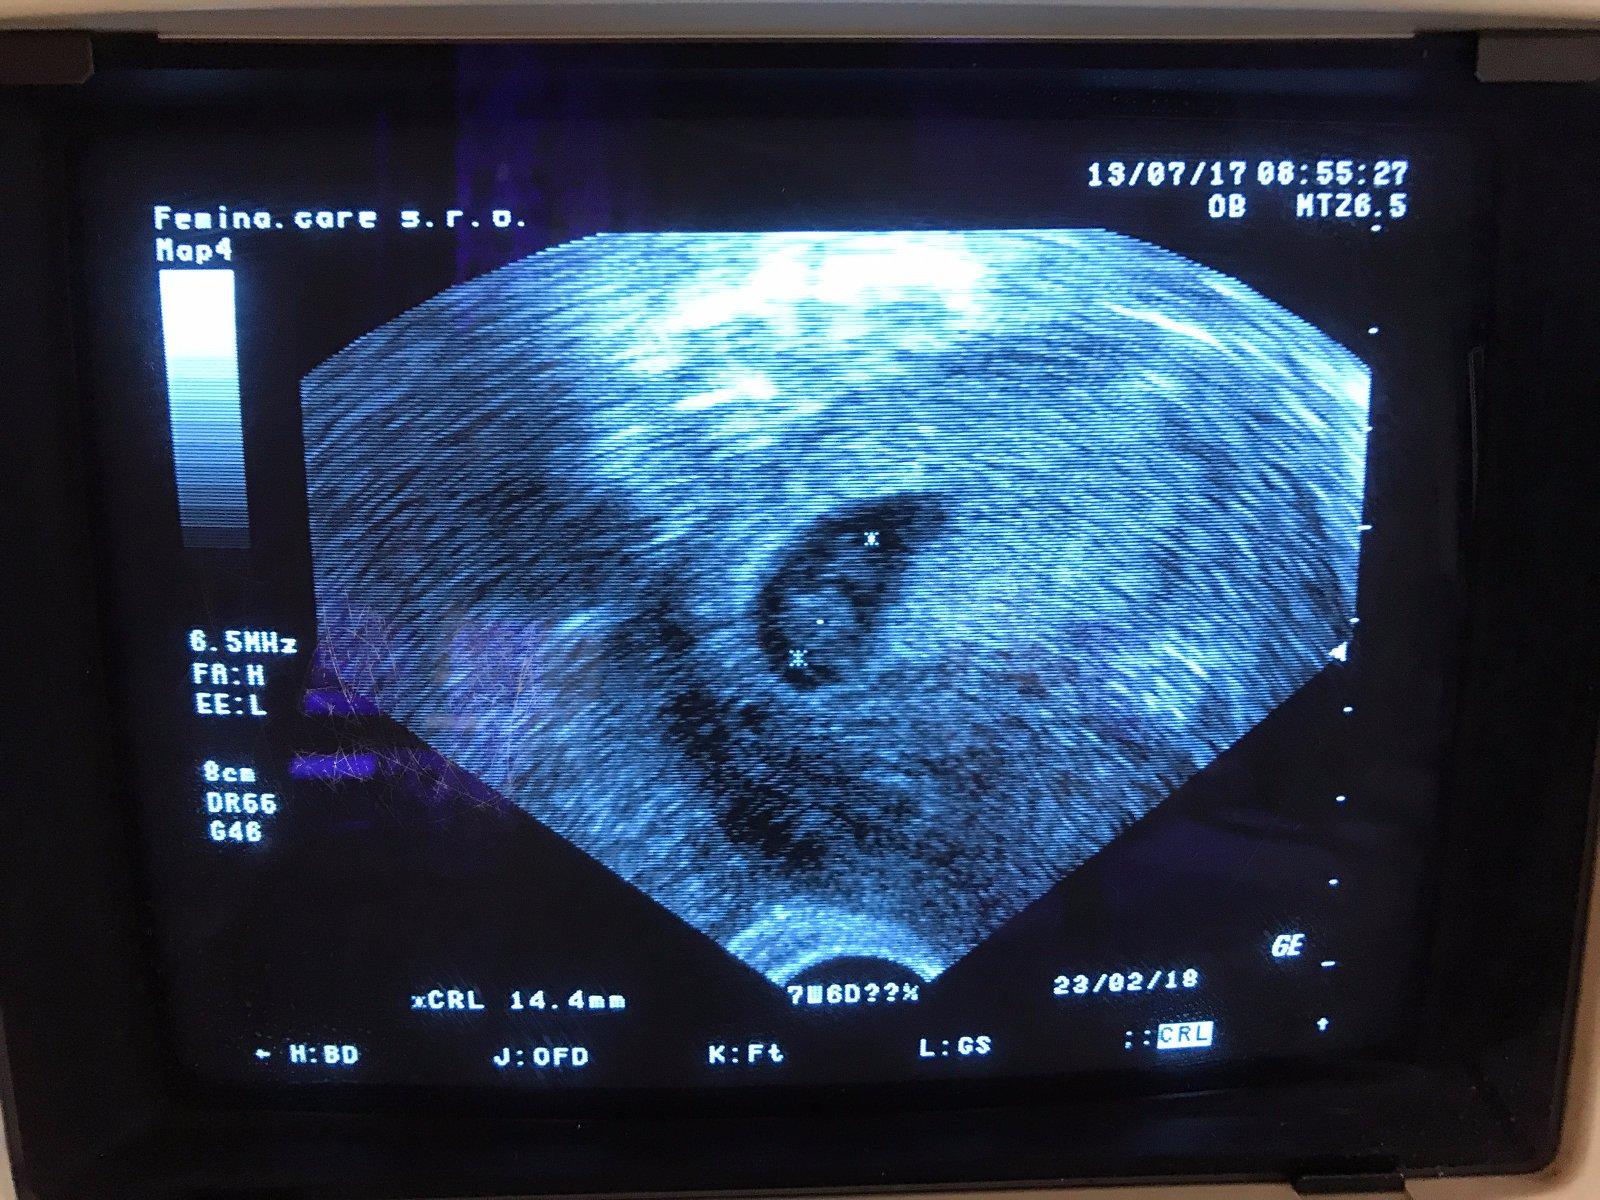

MAME SRDICKO!!!!! Od zari 2013 sme sa konecne dockali srdiecka! drka ma predpotopny UTZ, fotku som si robila sama z monitoru, dle ovu som 8+4tt a dle UTZ 7+6tt, ale sama mi povedala, ze ten utz nemeri presne. Kontrola 26.7. o 16.30h a dostanem prukajdu a pak sa mam objednat na screening do Brna. Mame hroznu radost a za odmenu sme mimiskovi kupili polodupky, 2 cepicky a dudlika!